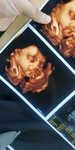

Mau tips biar bisa lahiran normal

Bagi tips untuk lahiran normal dan bisa memberi ASI pada buahhati